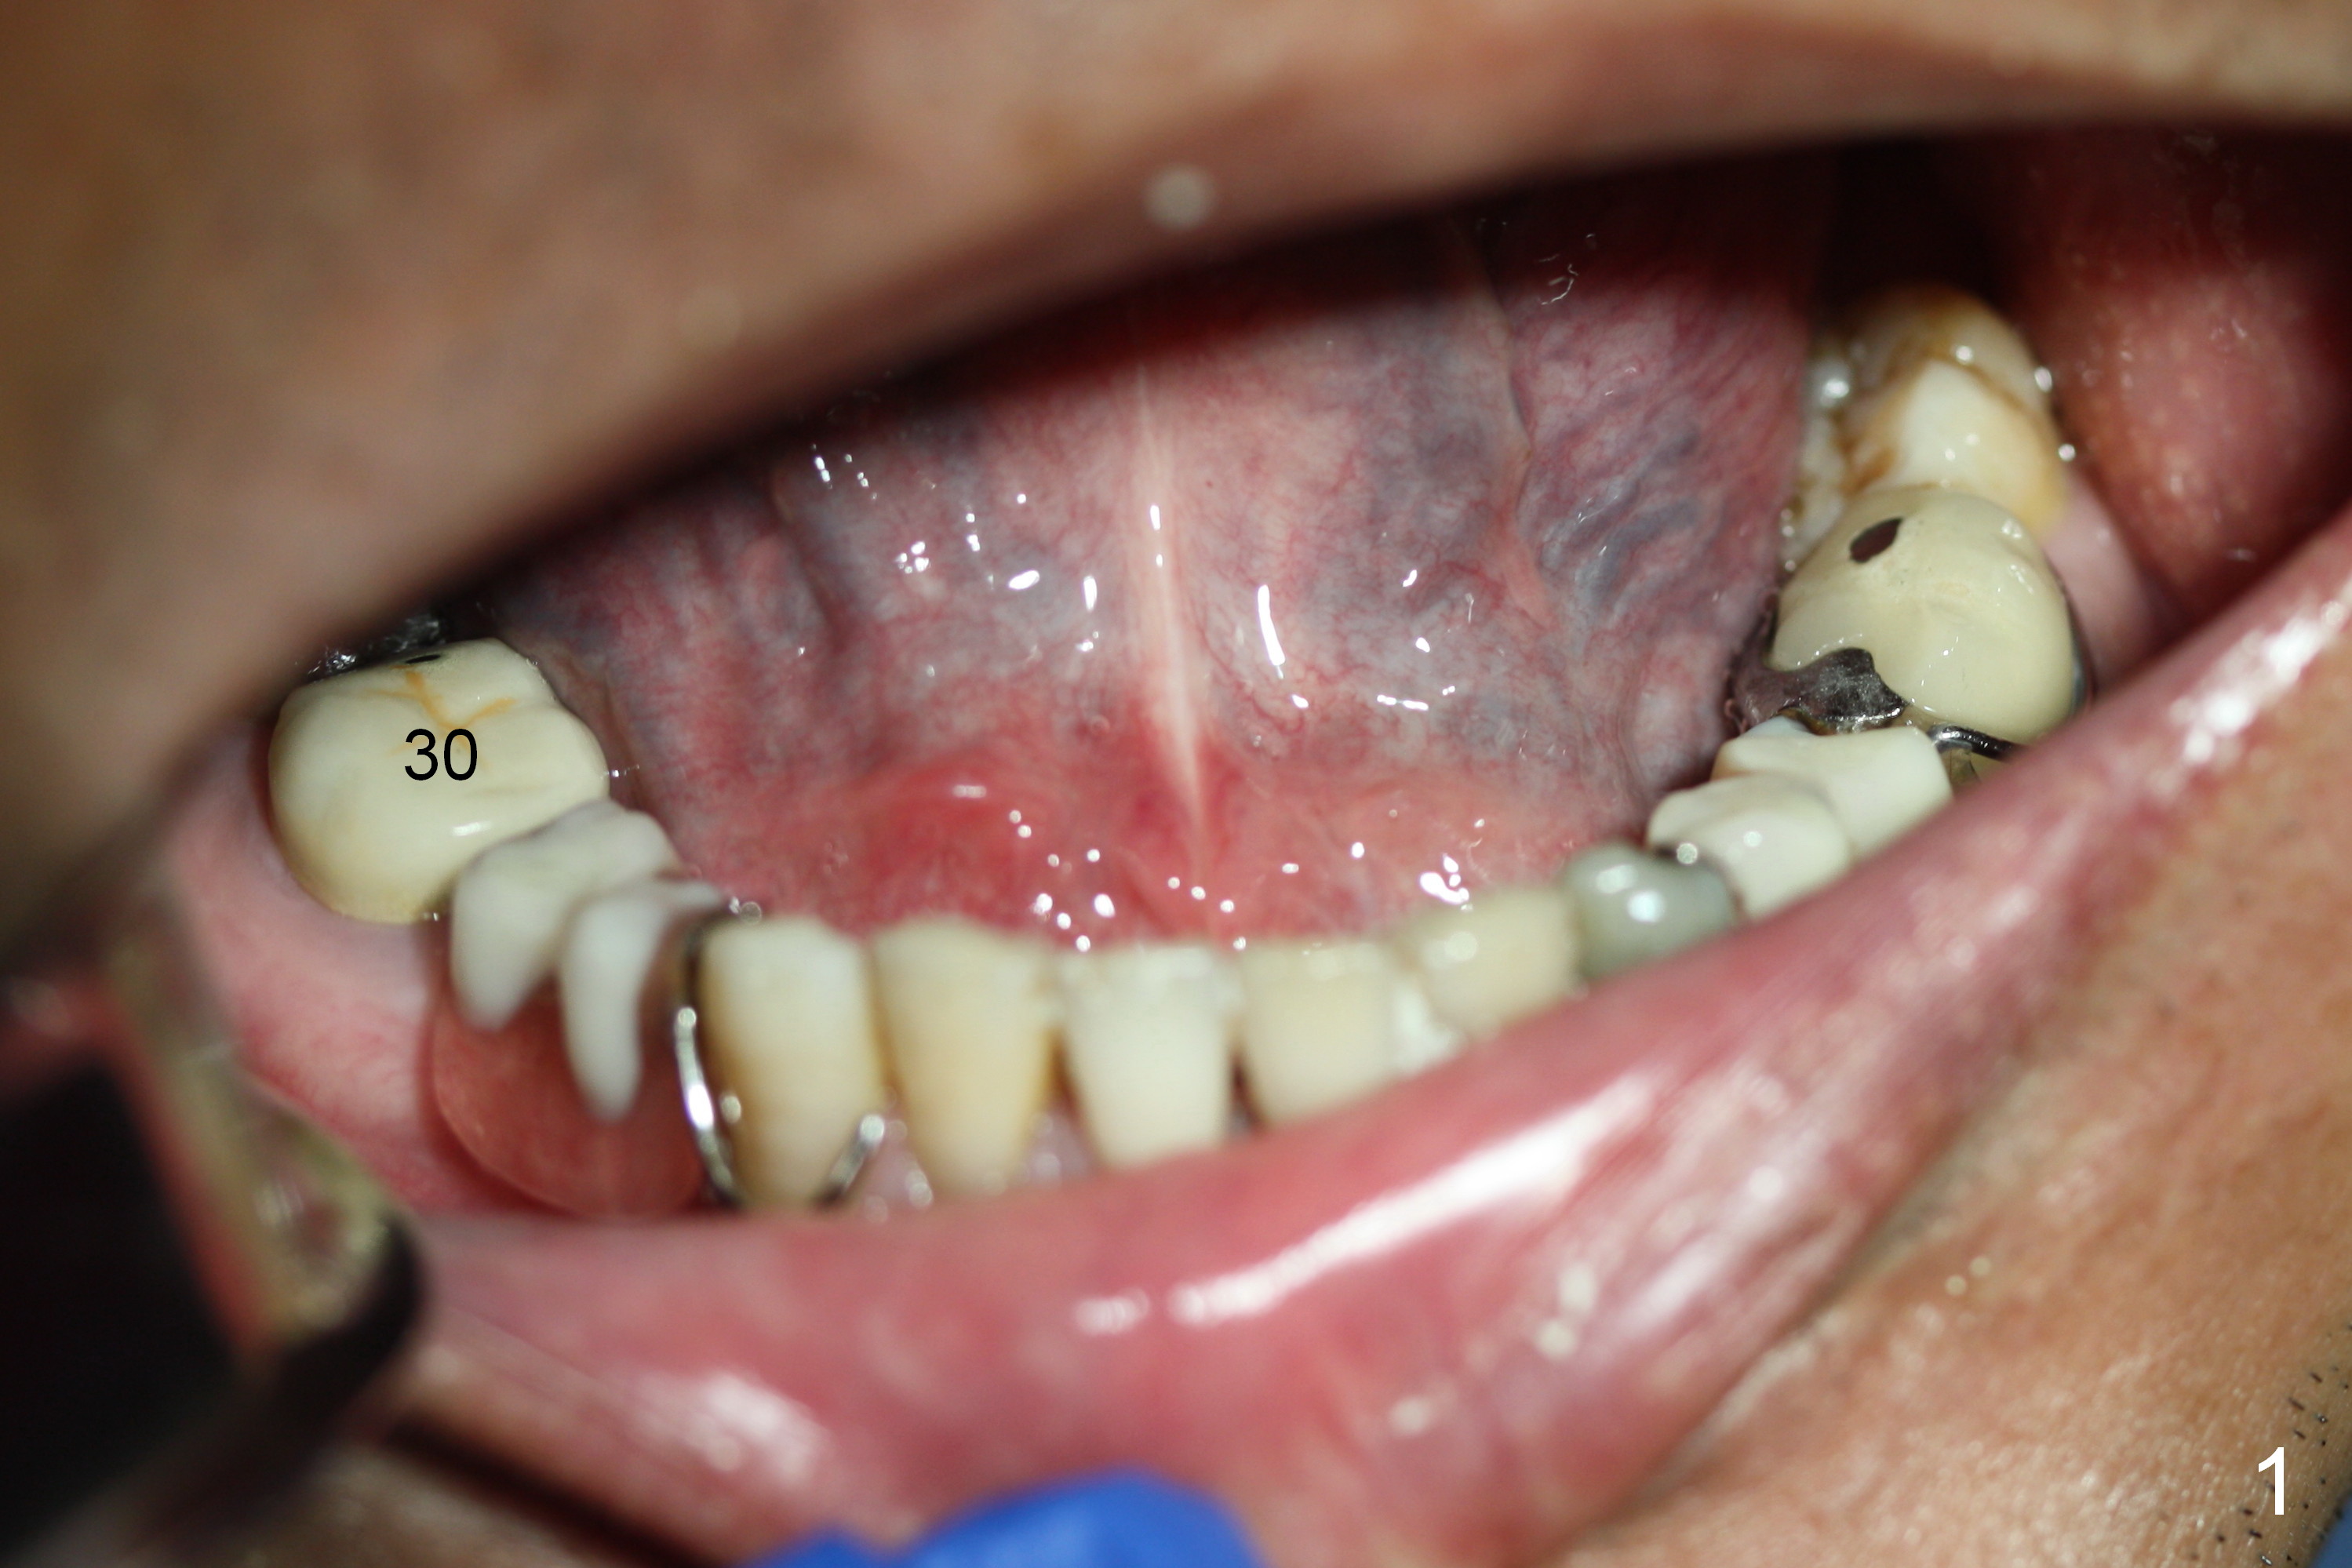

The patient has lost several teeth, which are replaced by removable partial dentures. He wants to have implants in the lower right first because of loss of a buccal clasp over the tooth #30 (Fig.1). When the lower partial is removed, a narrow soft tissue band is visible in the edentulous area. The hard tissue ridge is approximately 3 and 5 mm buccolingually at the sites of #28 and 29, respectively (Fig.3 after initial osteotomy). To place 2 adjoining implants at the same level, the treatment plan is modified: a 3 mm 1-piece implant will be placed at #28, while the plan at #29 remains the same: a 4.5 mm 2-piece implant.